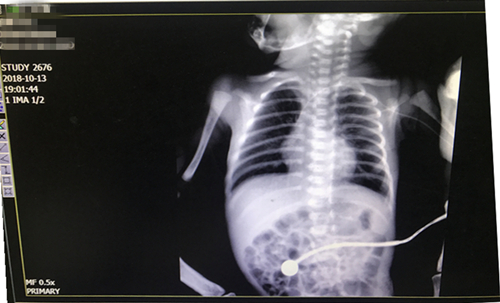

该技术操作过程较复杂,操作技术水平要求极高,置管过程中随时可能会出现呼吸、心跳骤停等危急情况。针对这一情况,在杨护士长到来之前,科室护理团队已将PICC置管需要的物品及抢救药物准备齐全,并制定出各种应急措施。新生儿科护士车棠和王昱与特邀专家分工协作,一针穿刺成功,同时急请放射科配合拍胸片确定导管位置,成功为该患儿实施了PICC置管术。此置管术为乐鱼在线登录入口首例新生儿PICC置管新技术。